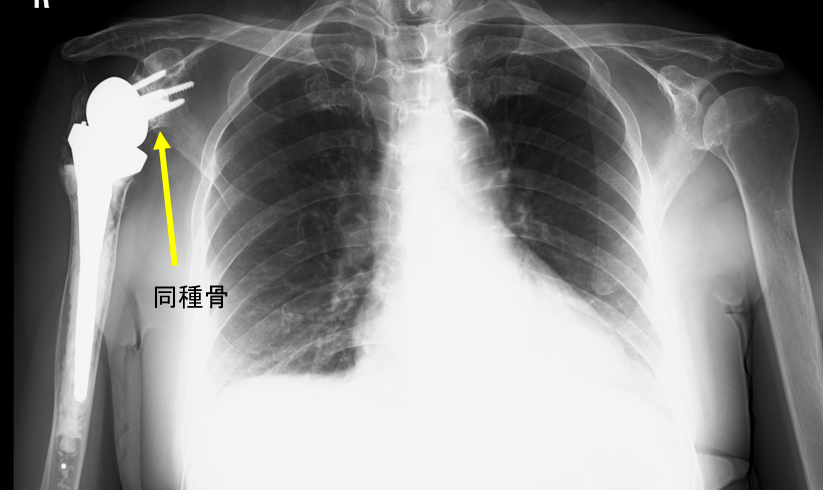

手術直後のレントゲン